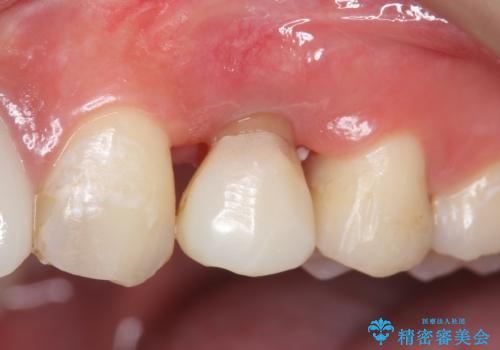

左上4の補綴物を除去したところ縁下歯質だったため、歯牙の挺出を提案し行いました。

挺出終了後は歯肉切除および骨外科により歯周組織を整え、オールセラミッククラウンによる補綴を行いました。